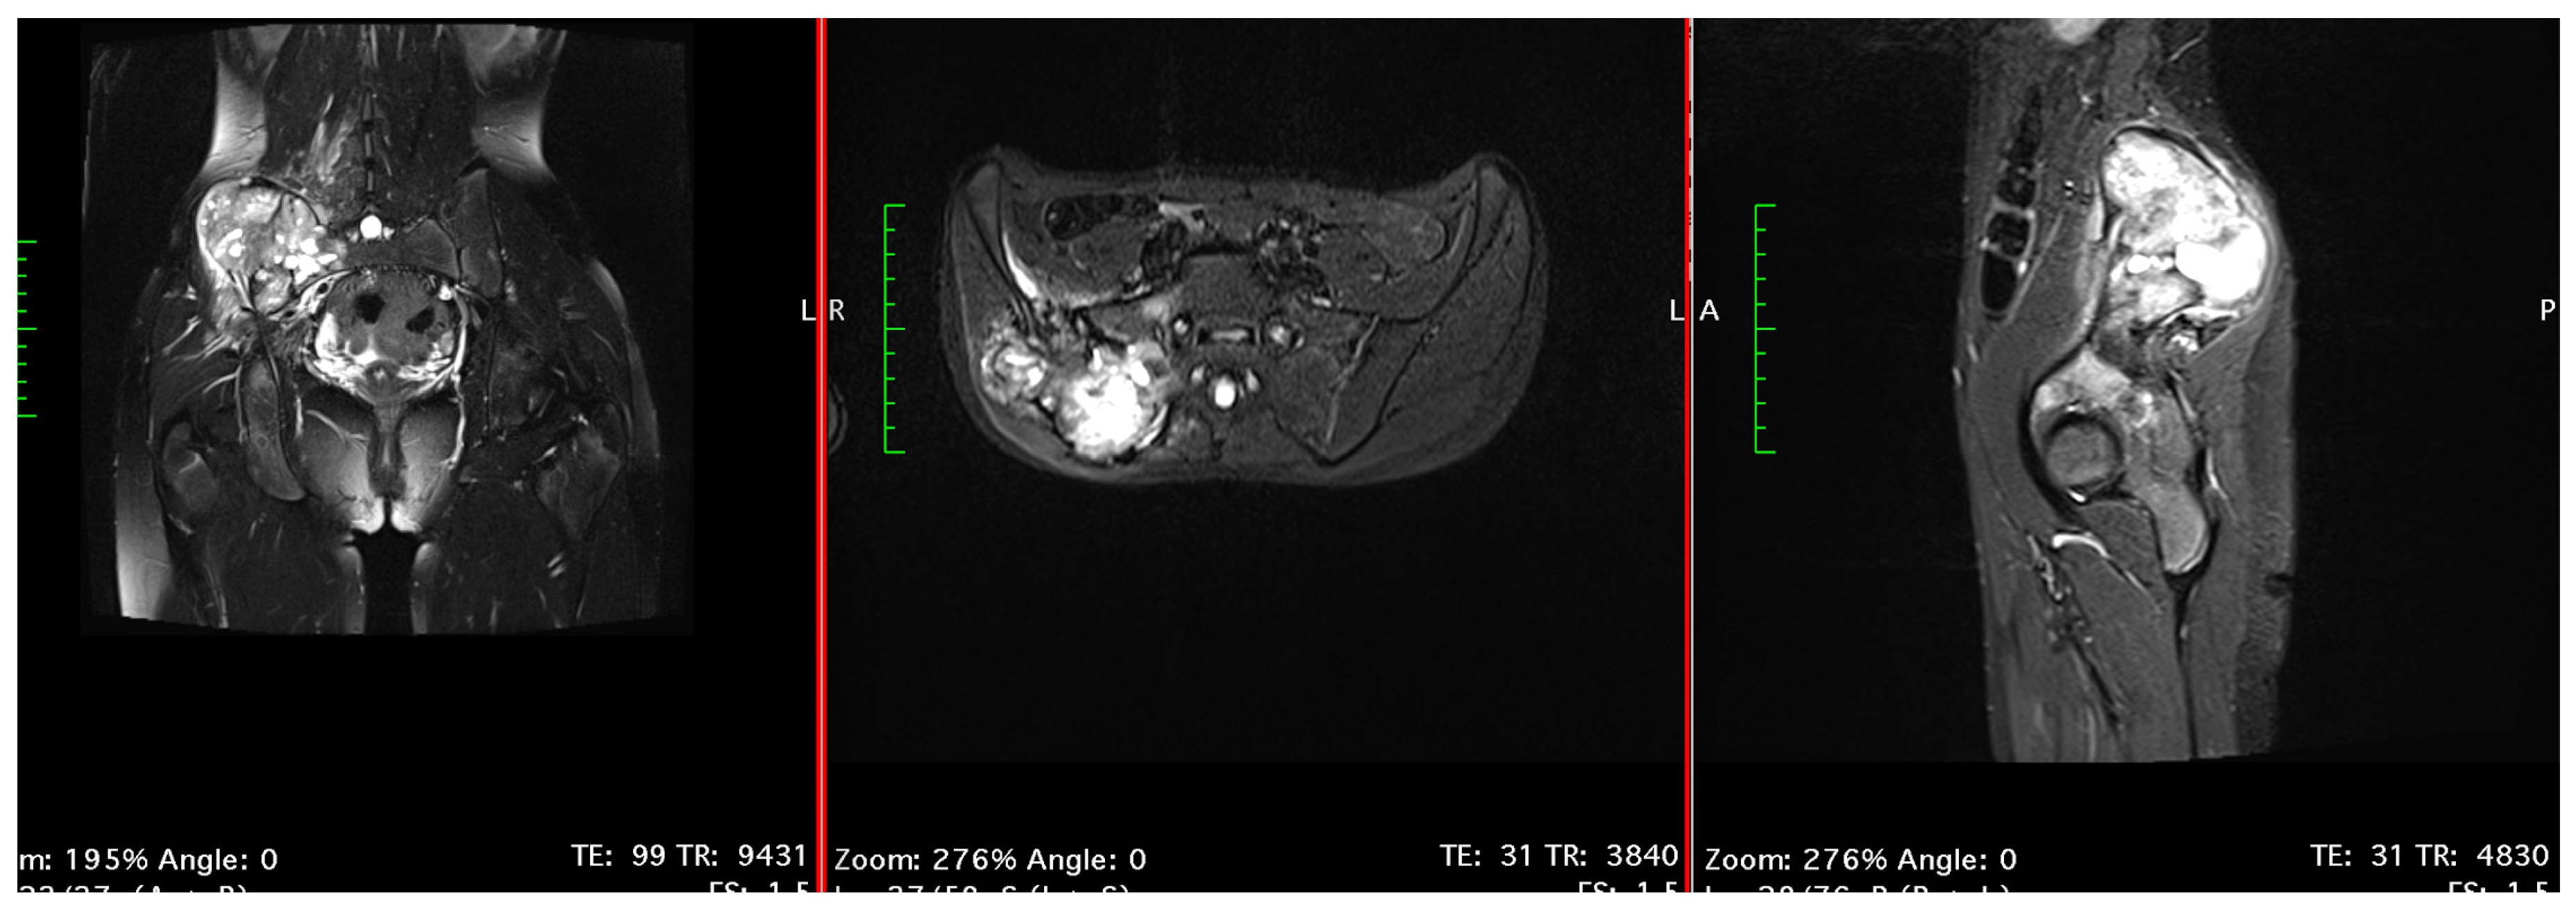

3.3.1. Pelvis Osteosarcoma